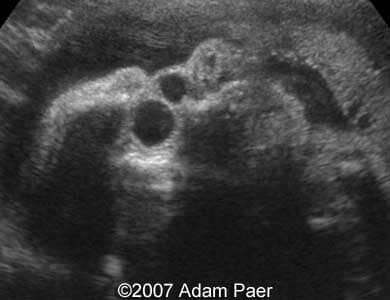

Dacryocystocele, unilateral Adam Paer, MD. Article Published: Jun 26, 2007 Costa Rica Case report These are some third trimester ultrasound images showing unilateral dacryocystocele..Images 1 and 2: Transverse scans at the level of the fetal eyes showing unilateral dacryocystocele. Images 3 and 4: Parasagittal scans showing dacryocystocele next to the eyeball. Image 5: 3D image showing small prominences of the medial canthus representing dacryocystocele. Discussion Board Start a discussion about this article Add to Favorites Favorite